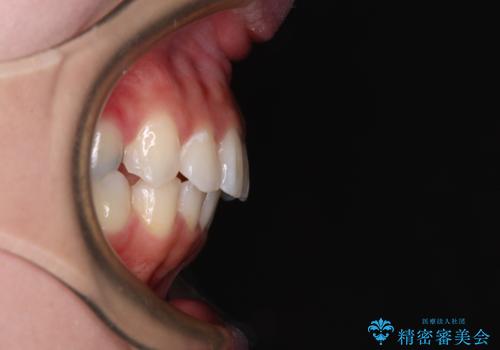

- 上の前歯が下唇に当たる感覚と奥歯の欠損を気にして来院された患者様です。

上顎前歯の突出感は、上顎全体が前方に位置していることが原因であったため、補助装置により上顎全体を後方に移動させることとしました。

上顎歯列全体を後方移動させたことで唇に当たる感覚は改善され、更には上下の正中位置も合わせることができました。